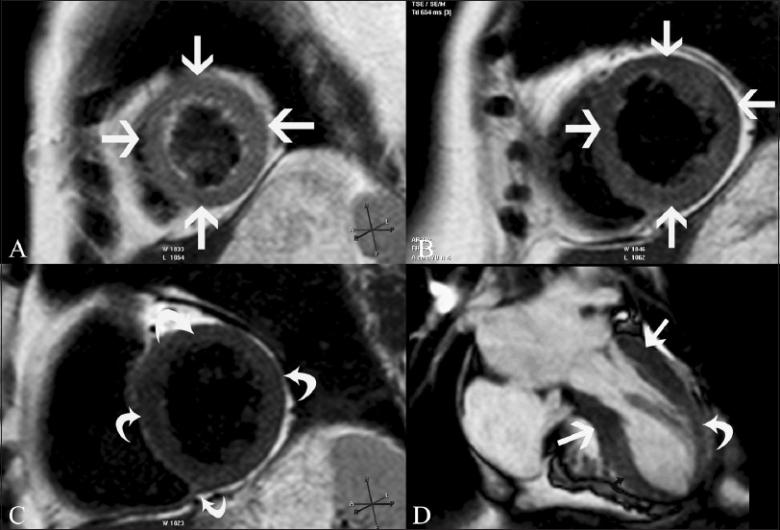

磁共振成像在评估心电图ST段抬高患者中的应用价值。

Utility of magnetic resonance imaging in the evaluation of patients with ST segment elevation on an electrocardiogram.

ST segment elevation is an important electrocardiographic (ECG) change that is typically found in acute myocardial infarction, but may also be seen in a variety of other conditions. MRI plays an important role in the evaluation of these patients. MRI not only establishes the diagnosis, which is essential for appropriate management, but also helps in the assessment of other factors that are important for risk stratification. In this review, we discuss the common and uncommon causes of ST segment elevation and the role of MRI in the evaluation of these disease processes.

摘要